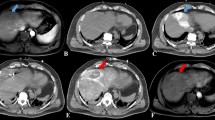

C-arm CT with hepatic arteriography was performed directly following the ablation to assess the ablation zone. Pre- and post-ablation C-arm CTs were fused using the XperGuide software to verify adequate margins (see Figs. 4 and 5). If margins were inadequate, the antenna was repositioned and additional ablation was performed. After ablation, the antenna was retracted during tract ablation. The catheter and sheath were removed, and the arterial puncture site was closed.

Example of a hypervascular hepatocellular carcinoma (HCC) ablation. A. Digital subtraction angiography of the right hepatic artery shows three hypervascular HCCs. B. C-arm CT with hepatic arteriography shows the first target lesion. C. Antenna in position. D and E. Fused pre- and post-ablation C-arm CTs depicting ablation margins

Example of a colorectal liver metastasis ablation. A. Solitary colorectal cancer liver metastasis only visible on diffusion weighted MRI (not visible on contrast-enhanced MRI). B. C-arm CT with hepatic arteriography clearly depicts the 11 mm lesion. C. Planning of trajectory. D. Ablation zone depicted with C-arm CT hepatic arteriography directly after ablation for 8 min at 120W. E and F. Fused pre- and post-ablation C-arm CTs in axial and coronal view show adequate margins

Firstly, since the procedure is performed entirely in the angiography suite, there is no need to transport the patient minimizing the risk of catheter luxation and removing the need to block a CT room. Also, any bleeding occurring during the procedure can be directly solved with embolization. Secondly, puncturing with C-arm guidance has the benefit of freedom in (multiplanar) angulation. It is easy to choose a puncture route out of the axial plane, for instance, with a caudo-cranial angulation, and even lesions high in the liver dome can be reached without traversing the lung or other non-target structures. This C-arm guidance is already installed on many angiography systems, obviating the need for expensive and often complex robotic systems [8,9,10]. A downside of this technique is that it requires fluoroscopy while the operator is placing the antenna, resulting in radiation exposure. Thirdly, HepACAGA allows for direct assessment of ablation margins. The ablation zone can be clearly depicted when performing a C-arm CT with hepatic arteriography directly after ablation. The ablation zone is then visible as an avascular area surrounded by a hyperemic rim. The XperGuide software is capable of semi-automatically fusing pre- and post-ablation C-arm CTs (see Figs. 4and5). Margins can be visually assessed and manually measured in multiple directions.